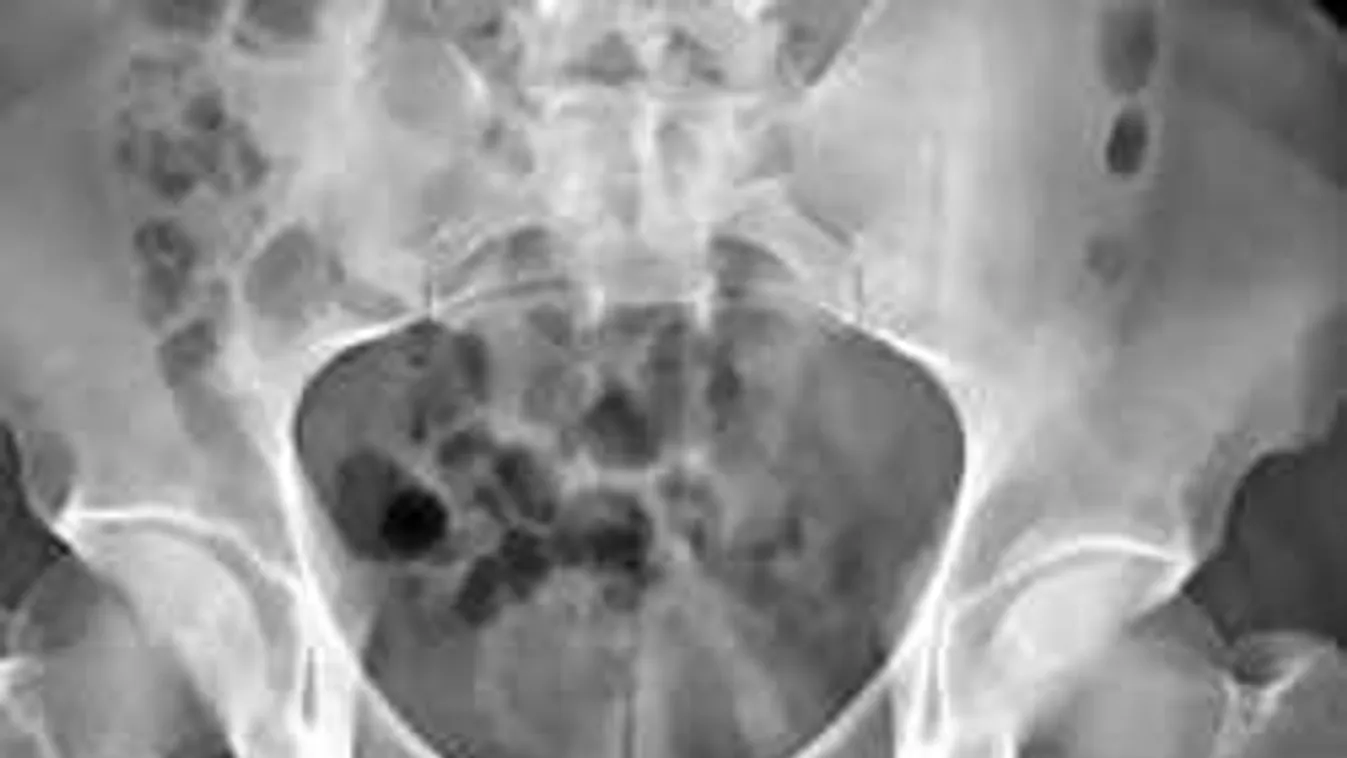

Az óriási dildó azonban a kelleténél jóval mélyebbre csúszott, és fájdalmas sérüléseket okozott a neve elhallgatását kérő illető húgyhólyagában. Ám a férfi először tudomást sem vett a kínzó gyötrelmekről, csak akkor ment el az orvoshoz, amikor 48 órával az incidens után észrevette, hogy véres a vizelete.

A Kaohsiung-i doktorok megállapították, hogy rossz helyen ragadt, rücskös eszköz komoly gyulladást okozott intim területen, végül sikerült eltávolítani, a harmincas éveiben járó férfi jelenleg otthon lábadozik.